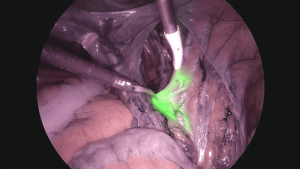

Patients often see Dr. Hrishikesh Pandit - Best Gynecologist In Ahmednagar for treatment of depression, counseling for Amniocentesis, Artificial Insemination, Avoiding Pregnancy Procedures, Birth Control Treatment, Breast Examination, Caesarean Section (C Section), Cervical Cerclage, Child Birth Education, Colposcopy Examination, D&C (Dilation and Curettage), Diseases in Pregnancy, Dysmenorrhea Treatment, Endometriosis Treatment, Female Disorder, Gynae Problems, High-Risk Pregnancy Care, Hysterectomy (Abdominal/Vaginal), Infertility Evaluation / Treatment, Infertility Specialist, Intra-Uterine Insemination (IUI), Laparoscopic Surgery, Management of Abortion, Management of Pregnancy, Maternal Care/ Checkup, Menopause Advice, Menopause Clinic, Menstrual Disorders in Adolescent Girls, MesoGlow, Mirena (Hormonal Iud), Normal Vaginal Delivery (NVD), Obstetrician, Obstetrics / Antenatal Care, Obstetrics Problems, Pap Smear, PCOD/PCOS Treatment, Pre and Post Delivery Care, Treatment of Breast Pain, Treatment of Cervicitis, Treatment of Heavy Periods, Treatment of Irregular Periods, Treatment of Miscarriage, Treatment of No Periods, Treatment of Ovarian Cysts, Treatment of Painful Periods, Treatment of Painful Sexual Intercourse, Treatment of Polycystic Ovary Syndrome, Treatment of Pregnancy and related Disorder, Treatment of Pregnancy Symptoms, Treatment of Vaginal Discharge, Treatment of Vaginal Itching, Tubectomy/Tubal Ligation, Unilateral Salpingo-Oophorectomy, Well Woman Healthcheck . For additional reasons, check the doctor's profile on Best Medi Cares.